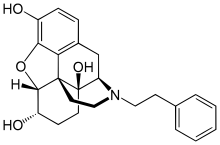

- N-Phenethylnormorphine

N-Phenethylnormorphine N-Phenethylnormorphine |